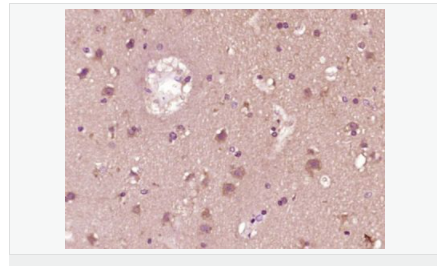

image.png